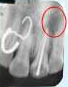

Regenerative Endodontic Procedure -

Regenerative Endodontic Procedure

Naseem Shah -

PRF Mediated REP in 21 with 18 Months Follow Up

Complete Bony Healing, Apex Closed, Lateral Wall Thickening- 15.5%